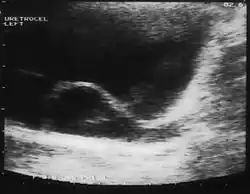

Since the advent of the ultrasound, most ureteroceles are diagnosed prenatally. The pediatric and adult conditions are often found incidentally, i.e., through diagnostic imaging performed for unrelated reasons.

A ureterocele is a congenital abnormality found in the ureter. In this condition the distal ureter balloons at its opening into the bladder, forming a sac-like pouch. It is most often associated with a duplicated collection system, where two ureters drain their respective kidney instead of one. Simple ureterocele, where the condition involves only a single ureter, represents only twenty percent of cases.